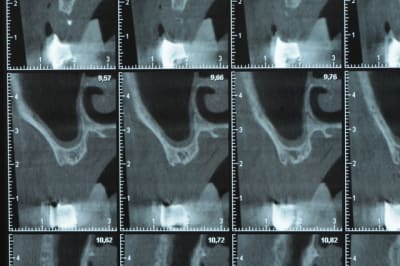

Une petite étude de ton cas D57

Sous réserves bien sur de voir l’animal en vrai

Les zones exploitables radiologiquement parlant:

Coupes implant

2,3 40100

4,96 35130 avec sinus lift mais difficile

5,25 35150

6,02 35130

6,78 35115 après réduction de hauteur de crête

7,26 35115 après réduction de hauteur de crête

8,51 35150

10,43 40115 ou 50115

11,10 40115

Ce qui nous fait 9 implants possible évidement avec un comblement de sinus on augmenterait encore les zones implantable mais ce n’est pas le but recherché, avec 8 (4+4) il doit être possible de faire une belle barre support de complet